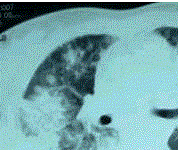

问题 患者女,23岁。间断发热伴皮疹1年半,诊断红斑狼疮。长期间断应用糖皮质激素治疗。近20 d来高热(T 39℃)伴咳嗽咳痰, CT(附图)示双肺满布圆形密度增高阴影,大小不等,密度不均匀,上、中肺野分布较多,双侧少量胸腔积液。血常规:WBC 2.52×10/L, N 0.62, Hb 92 g/L;ESR 40 mm/h;痰真菌培养:烟曲霉3次阳性;支气管镜检查右下叶、左舌段见黄色黏液性血性分泌物,毛刷找到霉菌孢子。 治疗时,不考虑应用

选项 A.二性霉素B B.卡泊芬净 C.伏立康唑 D.氟康唑 E.伊曲康唑

答案 D